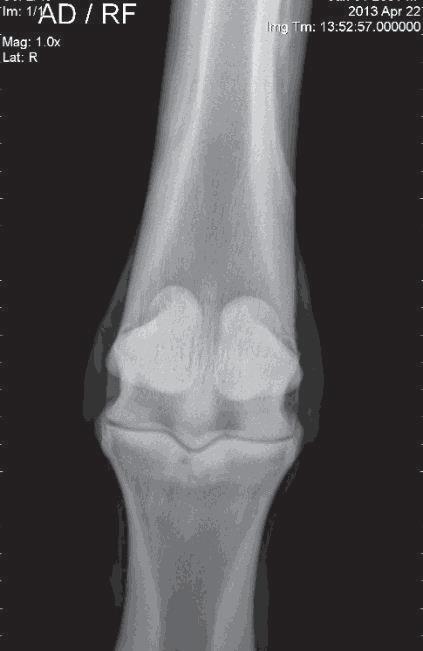

Figure 12: Purchase examination image on the left and lameness examination image on the right six months post-purchase that blocked to an abaxial sesamoid block. Area of sclerosis and region of subchondral injury of the sagittal groove of the proximal first phalanx (P1) which may be enhanced by a slightly flatter beam angle.

Image courtesy of Dr. Richard D. Mitchell.

Figure 13: Nuclear scintigraphic image (left) showing focal zone of IRU on the proximal aspect of the left front first phalanx (P1) and corresponding dorsal plane MRI STIR image demonstrating subchondral osseous fluid associated with subchondral bone injury which was associated with an incomplete sagittal sulcus fracture.